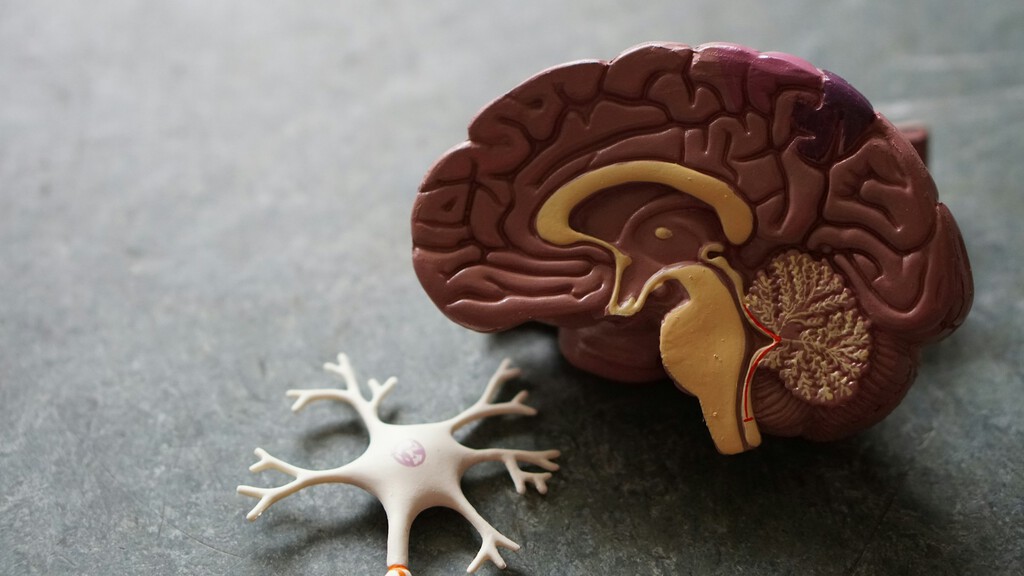

Implantes cerebrales que permiten a personas con parálisis mover un miembro o incluso jugar a un videojuego,...

Por ahora, estos logros son pruebas de concepto o pequeños ensayos clínicos que sirven para demostrar la...

Un equipo investigador de EE UU ha diseñado una proteína capaz de registrar las señales químicas entrantes...

Rafael Yuste defiende la “privacidad mental” como uno de los neuroderechos esenciales ante los avances tecnológicos y...

Un equipo internacional liderado por científicos en Australia ha creado por primera vez una imagen completa de...

La **memoria** no solo depende de la capacidad de recordar. Cada aprendizaje involucra un complejo sistema cerebral...